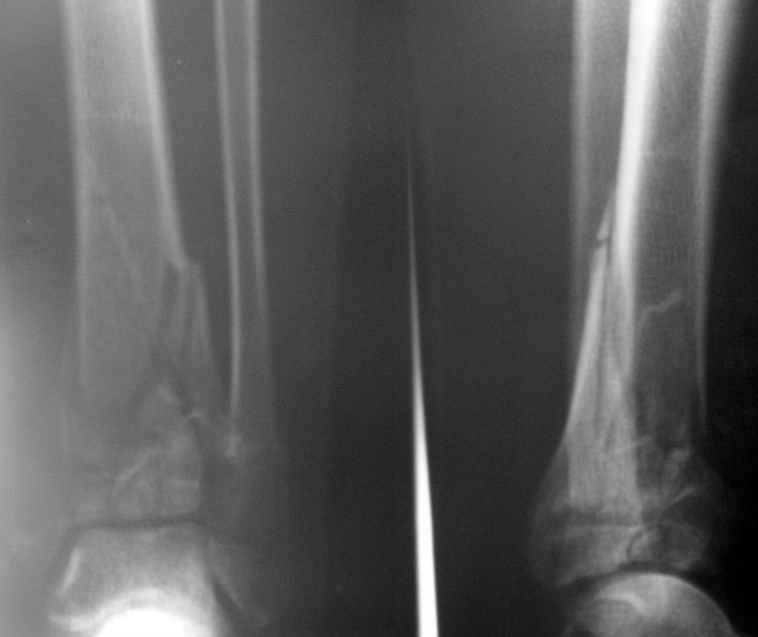

Глубокоуважаемые коллеги! Необходима ваша помощь.На консультацию обратился пациент 27 лет.

1,5 месяца назад при падении со скалы получил перелом пилона, лечился в районной больнице консервативно (циркулярная гипсовая повязка до средней 1/3 бедра). К нам попал только сегодня, сделали снимки и возник вопрос - делать ли что-то хирургически или уже пойти только на восстановительное лечение (продолжить иммобилизацию еще на 2-4 недели, потом разработка движений и т.п.)?Снимки прилагаю.

Уважаемые коллеги! Внутрисуставной перелом дистального конца б/б кости со смещением и подвывихом стопы должен был лечиться оперативно в раннем сроке.

По поводу обсуждаемого случая - 6-недельная фиксация такого перелома значительно увеличила шансы на артроз голеностопного сустава. Дальнейшая фиксация в гипсе практически сравняет эти шансы со 100%.

Если судить по представленной рентгенограмме, то, с учетом давности травмы, операция уже вряд ли необходима. Я бы продолжил гипс и назначил хондропротекторы и витамины.

После 7 недельного консервативного лечения дистального эпи-метафиза, Pylon type (кстати неплохой сустав)перелома, вряд ли поможет операция, наложить гипс на 3 недели и начать разработку сустава, ледующие снимки подскажут время нагрузки на конечность.